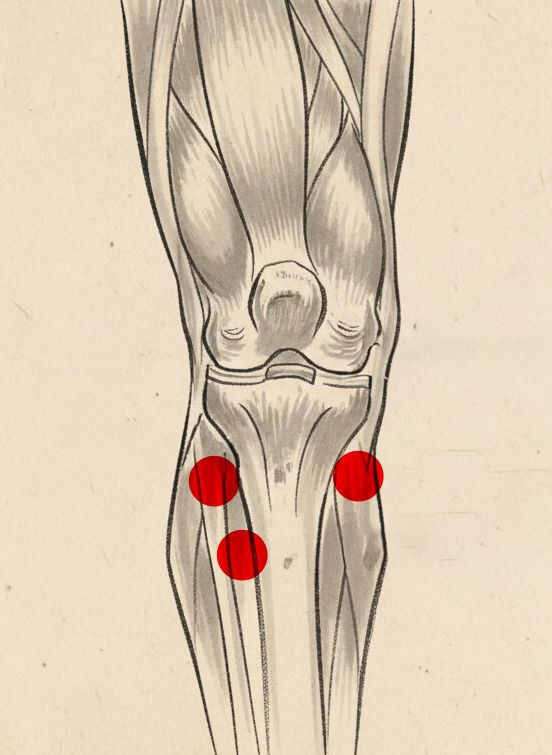

Magnesy o odpowiednio dobranym polu magnetycznym zostały

rozmieszczone dokładnie tam, gdzie znajdują się strategiczne

punkty akupresurowe stawu kolanowego, w tym punkty

ST36 (Zusanli), SP9 (Yinlingquan) czy

GB34 (Yanglingquan). Punkty te już w Tradycyjnej

Punktowy skoncentrowany nacisk na te punkty akupresurowe uruchamia intensywny detoks stawów kolanowych. Oczyszczają się powięzi i torebka stawowa, a organizm pozbywa się nagromadzonych toksyn, które są przyczyną bólu, sztywności i stanów zapalnych!

stymulacja punktów akupresurowych ST36, SP9 i GB34

stymulacja punktów akupresurowych ST36, SP9 i GB34